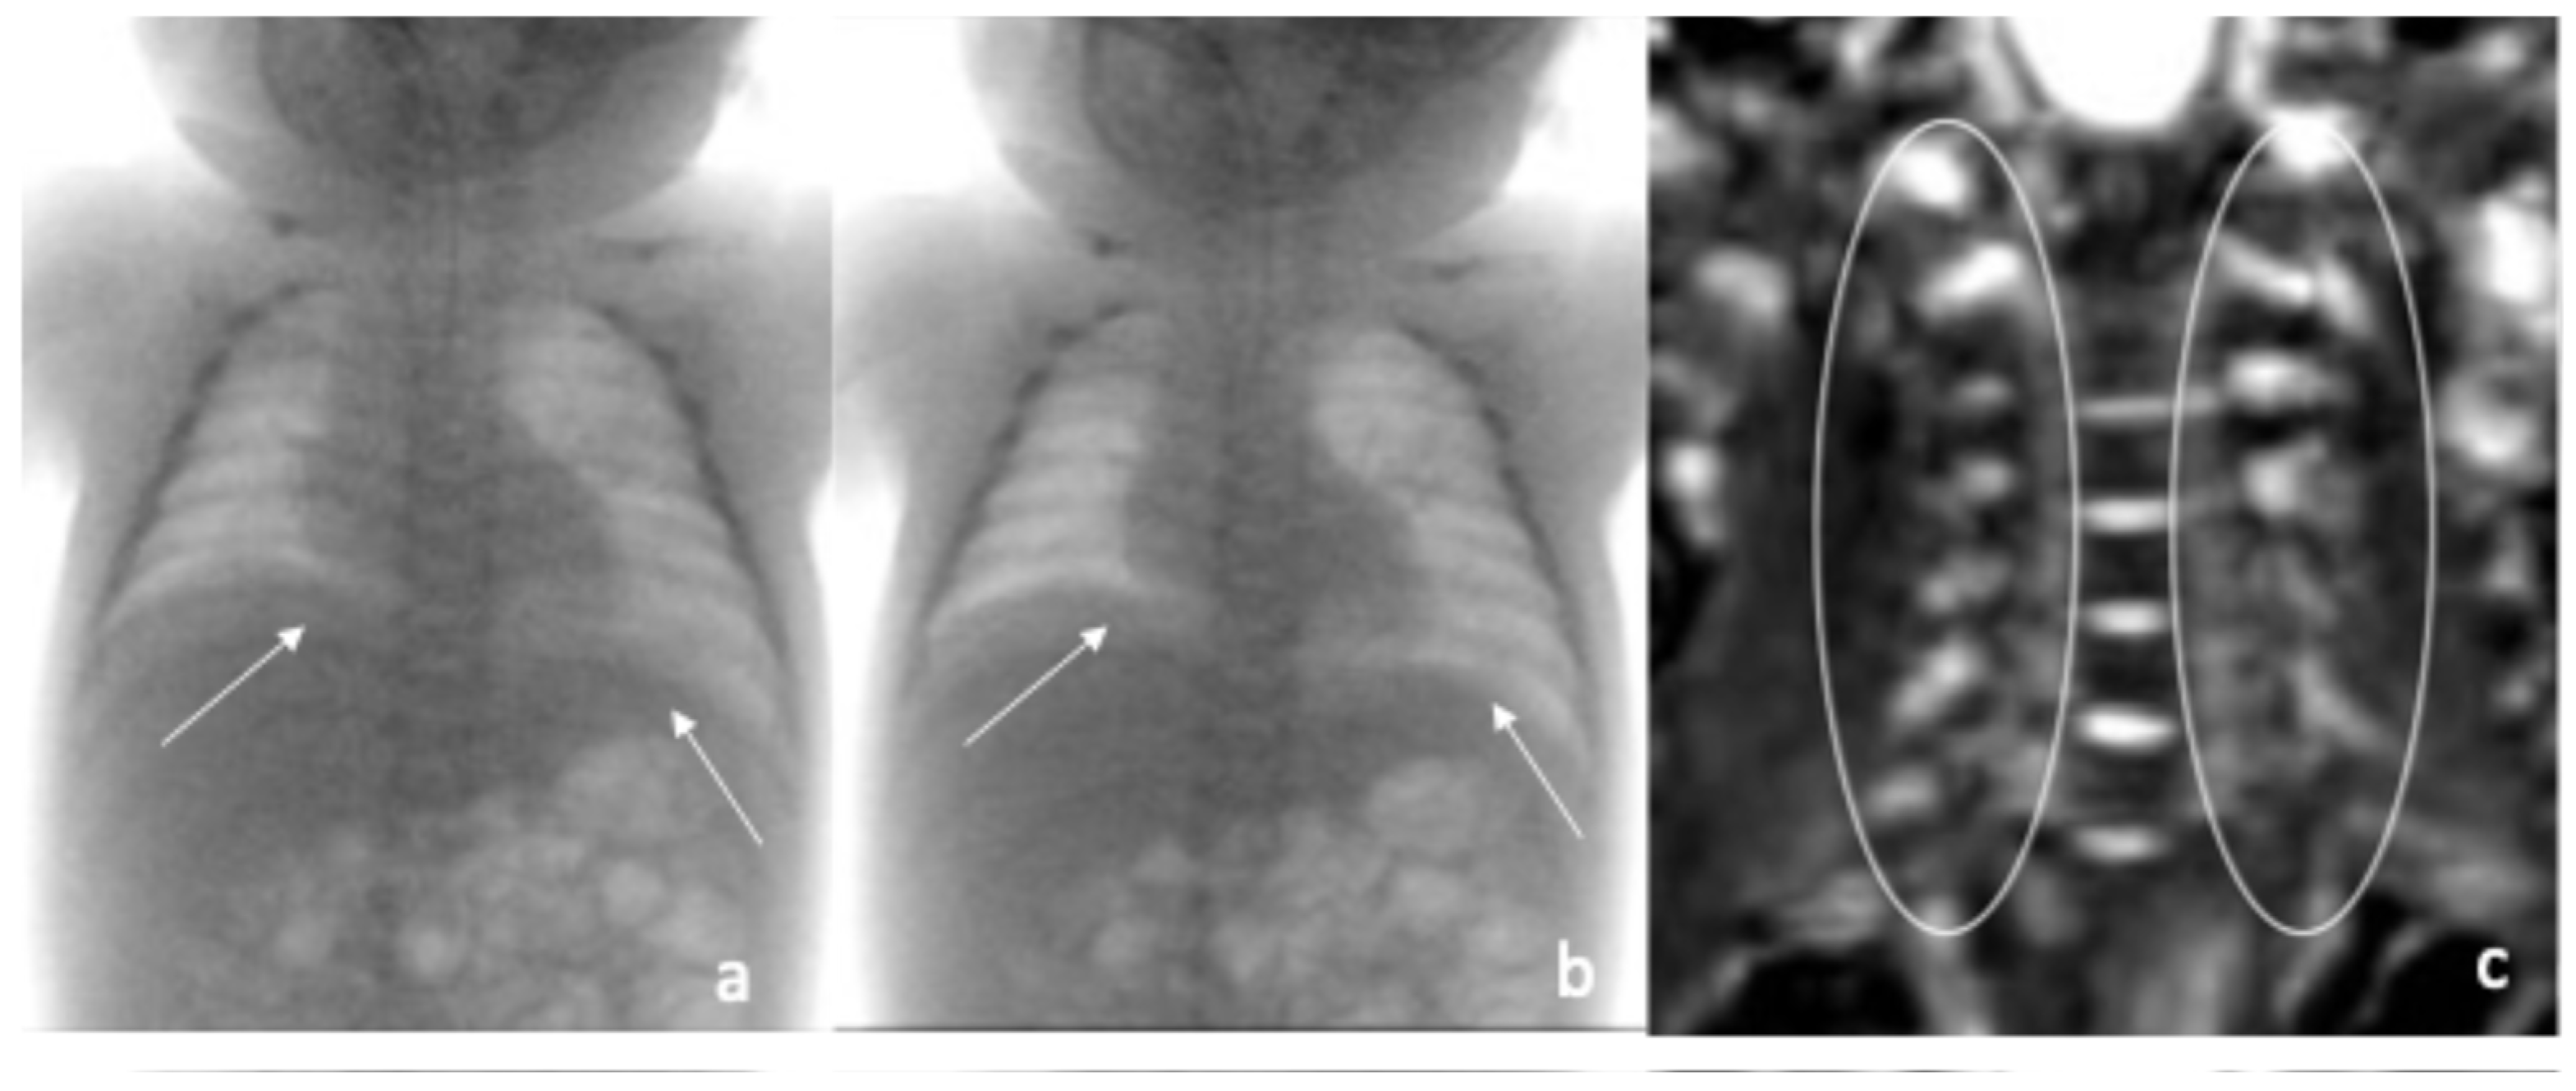

| Fluoroscopic evaluation | Inadequate bilateral diaphragm excursion | Reduced diaphragmatic excursion |